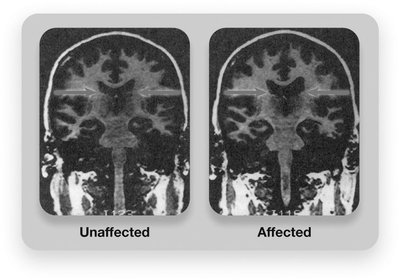

Brain structure: Larger ventricles, loss of brain tissue, differences in hippocampus and amygdala.

Brain activity: Reduced activity in frontal lobes and emotion/memory regions.